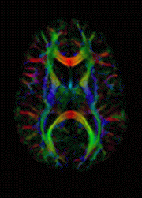

MRI image of white matter tracts

MRI is the investigative tool of choice for neurological cancers, as it has better resolution than CT and offers better visualization of the posterior fossa. The contrast provided between grey and white matter makes it the best choice for many conditions of the central nervous system, including demyelinating diseases, dementia, cerebrovascular disease, infectious diseases and epilepsy.[7] Since many images are taken milliseconds apart, it shows how the brain responds to different stimuli; researchers can then study both the functional and structural brain abnormalities in psychological disorders.[8] MRI is also used in mri-guided stereotactic surgery and radiosurgery for treatment of intracranial tumors, arteriovenous malformations and other surgically treatable conditions using a device known as the N-localizer.[9][10][11][12][13][14][15][16][17] [18][19][20][21][22]